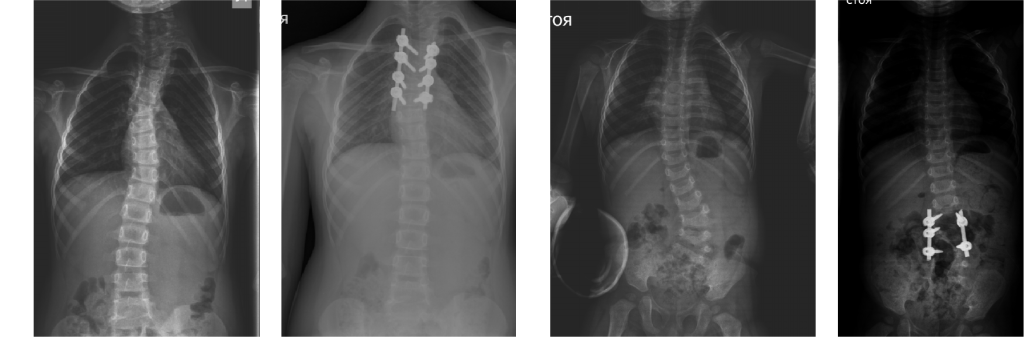

The Department is the only medical institution in the Russian Federation that performs a full range of diagnostic and therapeutic measures for children with destructive lesions of any part of the skeleton, including minimally invasive biopsies, immunological studies, histological and bacteriological verification.

The main principle of work: mandatory consideration of the child’s age characteristics and growth potential.

Technical capabilities: minimally invasive and reconstructive surgery technologies, bone plastic materials and instrumental fixation, modern power and ultrasound surgical equipment, navigation, neuromonitoring.

Main areas of surgical work: